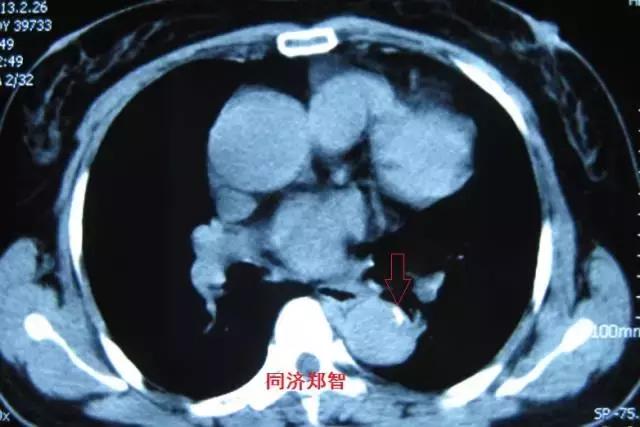

病例四

腹部平扫CT提示腹主动脉增宽,CTA证实为腹主动脉局限性夹层(红箭头所示)。